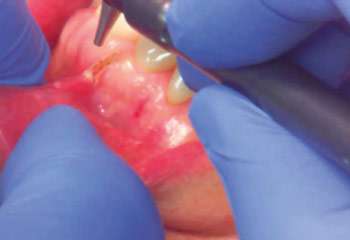

In another study, the CO2 laser was evaluated on 27 patients who underwent soft tissue pre-prosthetic surgery, including frenectomy, tuberosity reduction, hyperplasia removal, and sulcus deepening.4 The author pointed out that “it seems likely that discomfort is less after laser surgery than by more conventional techniques and it is definitely less than discomfort after conventional surgery with a secondary epithelialization technique. Swelling and edema were virtually nonexistent after laser surgery”. There was minimal swelling. The pain was moderate. A vestibular extension was created with mild-to-moderate discomfort, controlled with medium-strength analgesics. “For frenectomies, the main advantages appear to be speed and a clean, bloodless field… For palatal hyperplasia and soft tissue tuberosity reduction, the laser appears to be faster and cleaner with less discomfort than is normally associated with this form of surgery by other techniques”.[4] A third of the patients did not need analgesics. Reduced wound contraction was observed.

Niccoli-Filho et al.[38] described 15 cases where extensive epulis excision with maxillary or mandibular vestbuloplasty were carried out with a CO2 laser. Patients reported minimal discomfort during the first 24 hours after the surgery, in stark contrast with conventional surgery experience with complaints of significant pain, sialorrhaea, dysphonia, and dysphagia. For scalpel surgery patients, postoperative edema interfered with oral hygiene, further impairing healing. Overall, the study found that removal of epulis with the CO2 laser resulted in numerous notable improvements over conventional surgery, such as convenient removal of mucosa, lack of bleeding or need for sutures, and minimal postoperative pain and edema. In addition, the sites healed quickly, without complications, and both the esthetic and functional outcomes were excellent – all of the above allowed for more rapid placement of the final prosthesis.

Wlodawsky and Strauss[39] presented several clinical cases showing CO2 laser applications in intraoral surgery, such as mucocele excision, sialolithotomy, frenectomy, gingival hyperplasia removal, vestibuloplasty, aphthous ulcer treatment, leukoplakia treatment, and others. One of their conclusions was that “the low morbidity and minimal pain generally associated with laser ablation makes it a valuable tool in the management of premalignant mucosal lesions.” Similarly, Mason et al.[40] found low morbidity and minimal pain to be important post-operative outcomes following the removal of gingival fibromatosis. After the CO2 laser procedure, where the entire mouth was treated, no pressure packs were used and no sutures were placed. “Postoperative healing progressed with little discomfort or swelling and satisfactory improvement in gingival contour and aesthetics was achieved.”[40]